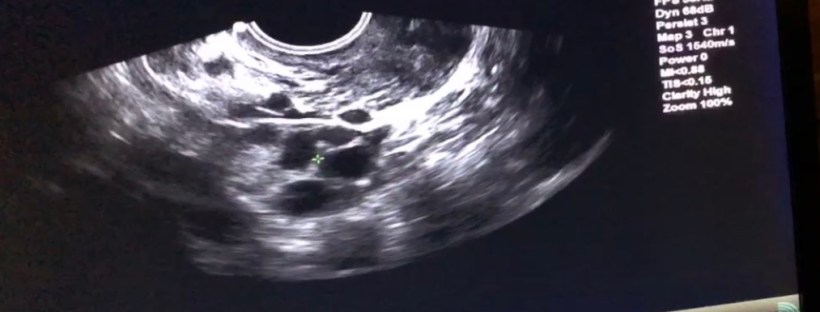

WHY I DECIDED TO FREEZE MY EGGS & MY JOURNEY TO FREEZE THEM

"If you want to make God laugh, tell him your plans." - Woody Allen When I was younger, I always thought by this age I'd be married and have kids. While that hasn't happened, I have lived in multiple cities in different states and countries, traveled around the world, had incredible experiences, met amazing people … Continue reading WHY I DECIDED TO FREEZE MY EGGS & MY JOURNEY TO FREEZE THEM